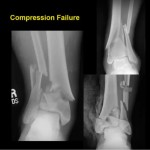

Pilon fractures- Anterior Approaches by Saqib Rehman MD- Part 2

Courtesy: Saqib Rehman MD Director of Orthopaedic Trauma Temple University Philadelphia Pennsylvania, USA www.orthoclips.com

Pilon fractures: Injury patterns and Surgical Planning by Saqib Rehman- Part 1

Courtesy: Dr Saqib Rehman MD Director of Orthopaedic Trauma Temple University, Philadelphia, Pennsylvania, USA